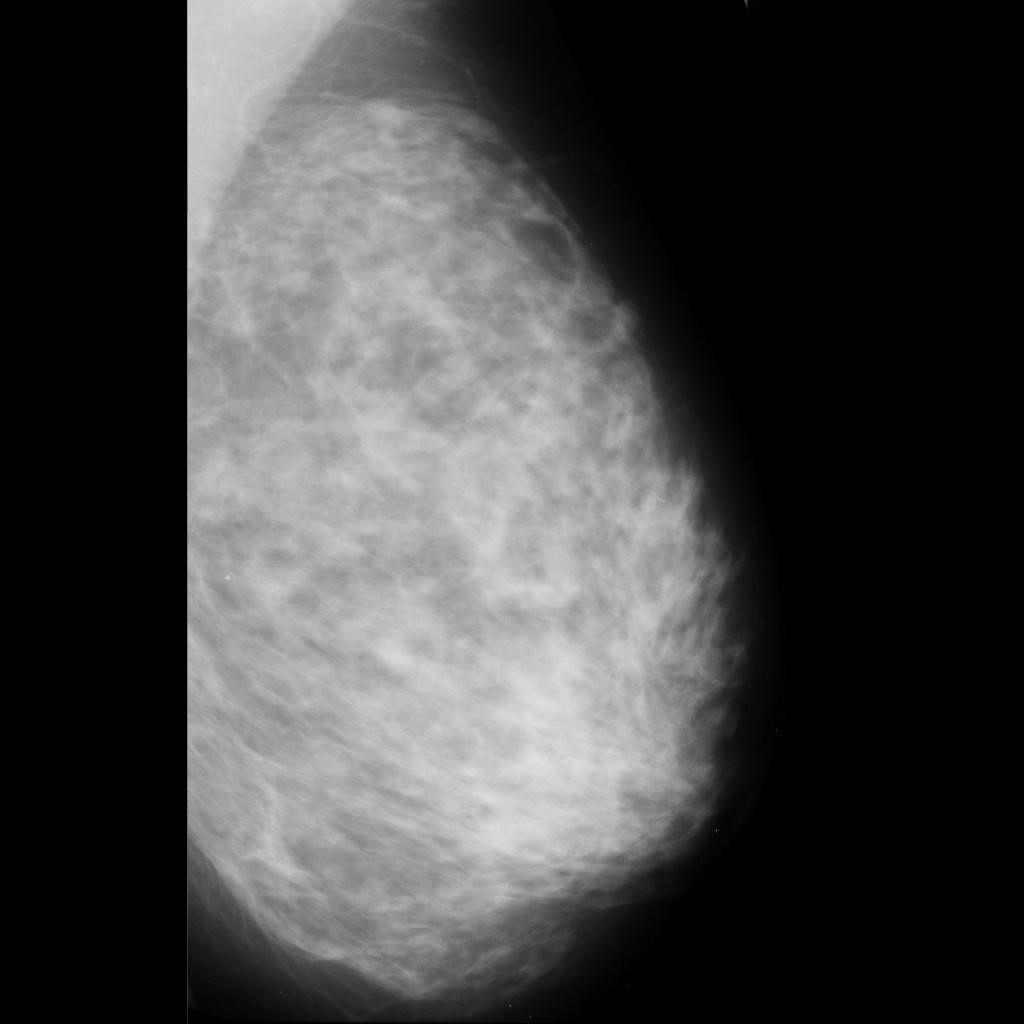

benign